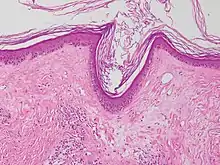

Micrograph of a vacuolar interface dermatitis with dermal mucin, as may be seen in lupus. H&E stain.